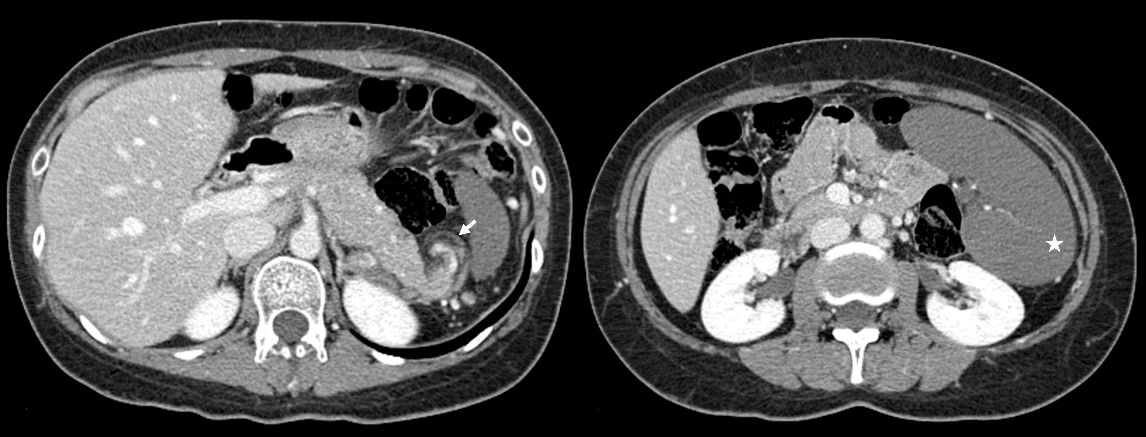

Although pain was alleviated with medication, an abdominal computed tomography (CT) was performed to exclude intra-abdominal adhesion since the patient had a previous appendectomy and presented with severe abdominal pain. The abdominal CT revealed heterogeneous parenchymal enhancement of the spleen and a whirl sign of the splenic hilum (Figure 1). The general surgeon examined the patient and, upon pain relief, the patient was discharged. The diagnosis at discharge was non-specific abdominal pain.

Figure 1.

Figure 1.— Abdominal CT at the time of the initial visit revealed heterogeneous parenchymal enhancement of the spleen and a whirl sign of the splenic hilum (arrow: whirl sign).